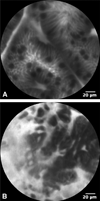

Background: Probe-based confocal laser endomicroscopy (pCLE) allows real-time detection of neoplastic Barrett's esophagus (BE) tissue. However, the accuracy of pCLE in real time has not yet been extensively evaluated.

Objective: To compare the sensitivity and specificity of pCLE in addition to high-definition white-light endoscopy (HD-WLE) with HD-WLE alone for the detection of high-grade dysplasia (HGD) and early carcinoma (EC) in BE.